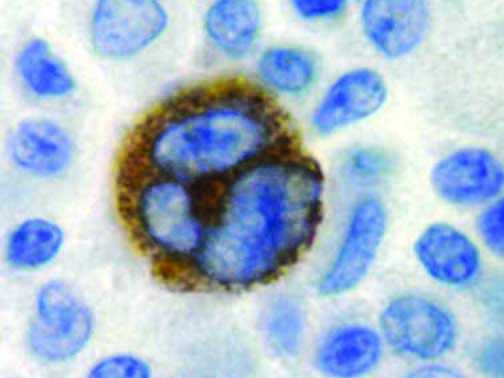

It is the ICU physician who is most likely to witness one of the deadliest manifestations of the abnormal immunological response, the cytokine storm syndrome (CSS). This response is also referred to by some as the cytokine release syndrome (CRS). CSS is characterized by continuous activation and expansion of macrophage and lymphocyte populations, which secrete large amounts of cytokines, causing the cytokine storm. This massive cytokine release is akin to hemophagocytic lymphohistiocytosis (HLH) disease, a syndrome characterized by initial unchecked and persistent activation of cytotoxic T lymphocytes and NK cells.

Clinical and laboratory manifestations of HLH include fever, enlarged liver and/or spleen, neurologic dysfunction, coagulopathy, liver dysfunction, cytopenias (i.e., low levels of erythrocytes, leukocytes, and/or platelets), hypertriglyceridemia, hyperferritinemia, hemophagocytosis, and eventually diminished NK cell activity as the immune system becomes progressively paralyzed. HLH can be familial (primary HLH) or secondary to another disease process (sHLH), such as rheumatic disease, in which it is referred to as macrophage activation syndrome (MAS, characterized by elevated ferritin).